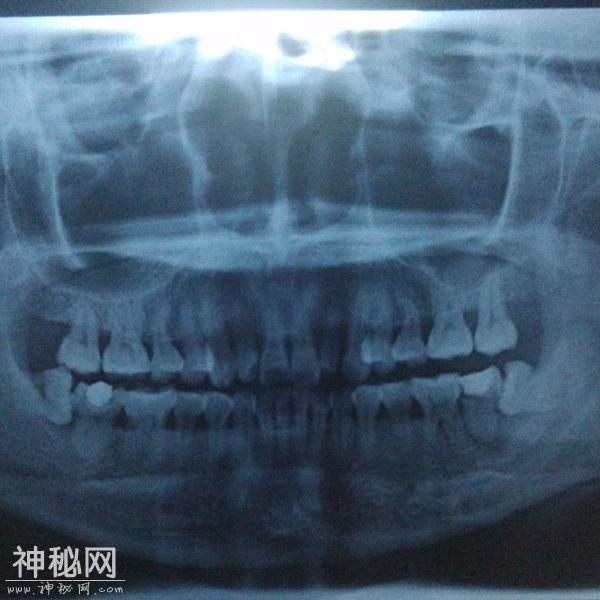

首先并不是每个人都有机会萌出全部四颗智齿,如果某一颗没有对生的,有可能会造成对位的口腔黏膜磨损,多见于下位。 其次,阻生智齿一定要拔除。阻生简而言之就是你的口腔骨骼没有给那颗牙留足够的位置,这样智齿就会用把兄弟姐妹往旁边挤的粗暴方式长出来。这个过程中,任何的外界刺激,食物残渣残留都可能造成严重感染,

这种情况下就一定要先消炎然后拔除。否则以后你每次发烧感冒都可能使智齿感染,反过来也一样。 一般来说阻生智齿拔除不是大手术,上牙比下牙好拔除,但依据你的牙齿状况,过程可能持续10到15分钟,一定会打麻药,麻药负责你那半边脸的痛感缺失。手术过程中首先要划开牙龈,然后非常可能用到锤子和其他工具把牙撬出,或如果你的牙形比较细长,可能直接敲碎拿镊子夹出。手术风险:如果你的牙根非常长,长到和其下的神经有粘连,可能导致局部的永久性麻痹。术后:每个医生都会告诉你多久拿掉填充物多久可以刷牙。

最好提前拍牙片,看一下智齿生长方向,我是横着长得,而且与神经和下颌骨粘连,当时拔了一个多小时,小时钻,敲,橇,再重复,总之各种恐惧害怕,多亏大夫和护士逗我,要不害怕的血都止不住,拔不了,所以说有智齿我是建议早拔,不要拖